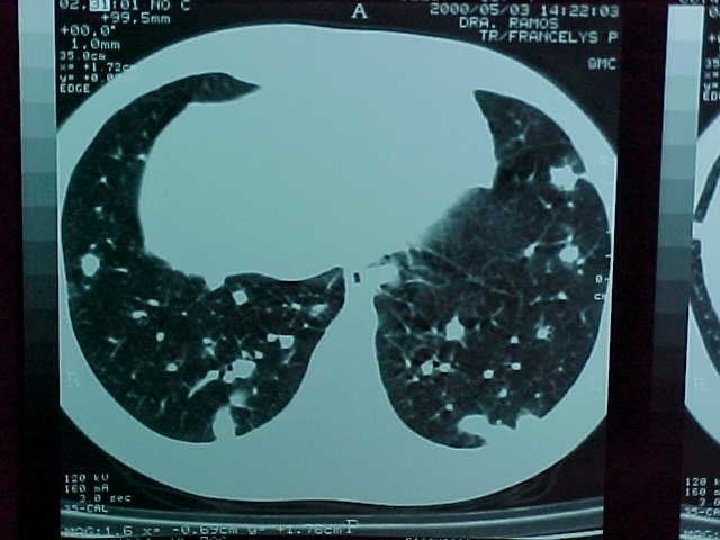

Histoplasmosis asociada a cueva en Venezuela Resultados: 28 estudiantes (17 hembras y 11 varones; rango de edad entre 15 -18 años con una media de 17 años) *20 (71. 4%) desarrollaron enfermedad aguda -64. 3% dentro de los 10 -28 días (mediana 14 días) posterior a la exposición. *2 (7. 1%) asintomáticos, tuvieron alteraciones radiológicas y en la serología para histoplasmosis.

Histoplasmosis asociada a cueva en Venezuela Resultados: 20 estudiantes enfermos-síntomas *Fiebre (77. 7%) *Dolor abdominal (38. 8%) *Tos no productiva (72. 2%) *Astenia (33. 3%) *Cefalea (66. 6%) *Dolor torácico (22. 2%) *Nauseas y vómitos (50%) *Disnea (16. 6%) *Rash (38. 8%) *Mialgias (16. 6%) *Eritema Nodoso (5. 5%)

Histoplasmosis asociada a cueva en Venezuela Conclusiones 1. -Aunque la cueva no es ambientalmente favorable para la transmisión de Histoplasmosis, por su elevada humedad interna predominante durante gran parte del año, el gran porcentaje de personas del grupo estudiado que desarrolló infección y enfermedad clínica en relación con una exposición ambiental relativamente breve, es indicativo de la ocurrencia de un elevado inóculo 2. -Este reporte constituye el más grande de los registrados en la literatura mundial